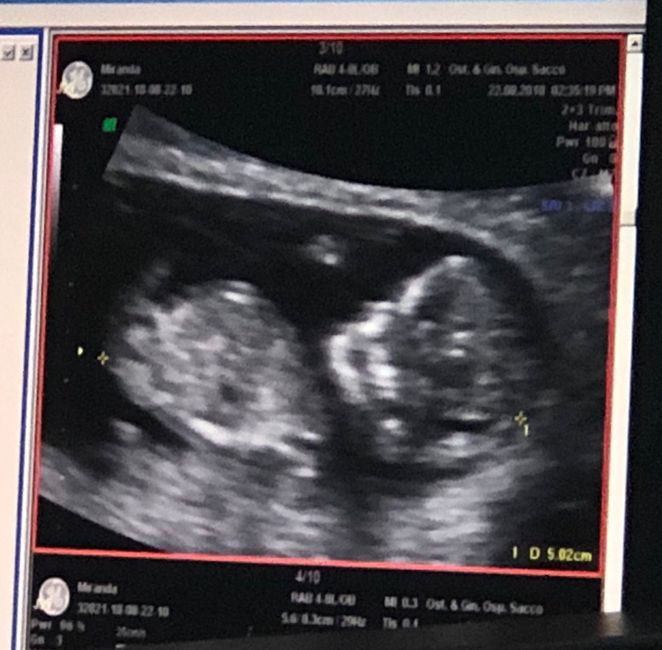

Ho caricato una foto nel post di Deborah

Scriviamo accanto alla foto di quante settimane siamo.. V va?? Inizio io 12+6